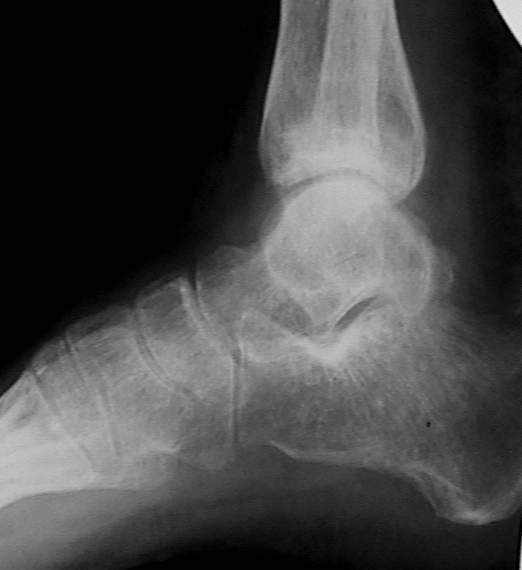

У больного травма в августе 2001 г. Лечился консервативно, Проводилась иммобилизация гипсовой лонгетой 3 мес. В последующем местное лечение. Остается контрактура боли в области наружной лодыжки. Направлен в наше отделение в конце января 2002 г Планируется костная аутопластика, остеосинтез пластиной, винтами перелома наружной лодыжки. Решается вопрос о коррекции неправильно сросшегося перелома внутренней лодыжки. Рентгенограммы: фас; профиль; план Сергей Зырянов